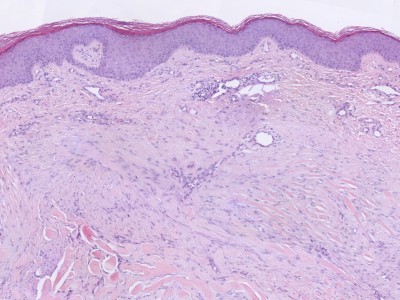

| Histologie |

actine positieve myofibroblasten collageenbundels parallel

aan epidermis |

verminderde apoptose collageenbundels parallel en nodulair

toename bloedvaten |